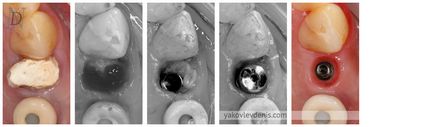

Átvágása után kialakult fogíny csappantyú hozzáférést a csont. Továbbá, a helyzet az implantátum és buduyuschego pilot fúró készül benyújtani a csontban. Ezután egy speciális furat van kialakítva, szigorúan a formáját a kiválasztott implantátumot. Az implantátum készlet egy bizonyos erővel, akkor a dugó be van csavarva az implantátum (ahelyett, hogy a felfekvési), és a gumiszerű összevarrtuk. fogíny gyógyulás 10-14 napon belül, amely előírja a második látogatás az orvos eltávolítására varratokat. Miután varratszedés több hónapig fog beültetése az implantátum a csontszövet. Az orvos ezután ismét tesz egy kis bemetszést gumik, eltávolítja a kupakot, és létrehozza az úgynevezett gyógyító pillér - egy elem, amely kiáll a gumi, és egy kör alakú alakjának megfelelő a jövő nem a fogat. A formáció fogíny kontúrok alkalmazni ideiglenes műanyag korona, ami már tud rágni. Azt is szükség van, hogy ellenőrizze a terhelés előtt az állandó fogpótlás.

Bizonyos helyzetekben, fogíny jából úgy állapítják meg, a beültetéssel, hogy csökkentse a kezelés időtartama.

Pillér - része a fogászati implantátum, amely rögzített korona vagy protézis.

Ütközők is különbözőek:

- a gyártási módszer: gyári (gyári tétel gyártott, a standard kivitel) és az egyes (gyártó speciálisan az egyes betegek);

- az anyag gyártási: titán-alapú ötvözetek, kobalt-króm, a cirkónium-dioxid kerámia e.max, valamint a műanyag;

Egyedi ütköző lehetővé teszi, hogy a hatás a természetes fog, az íny, hogy támogatást (a széle a fogíny, mint a természetes fogak és fogíny szemölcsök).

A szabványos ütközők esztétikailag elfogadhatatlan egy olyan fontos terület, hiszen nem támogatják a képesség, hogy a lágy szövetek és utánozzák a természetes kontúrjai a természetes fog.